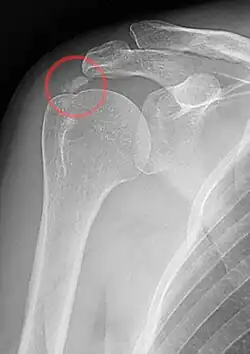

Die Diagnose wird gestellt durch Schulterschmerzen, die auf eine „Verkalkung“ in der Rotatorenmanschette zurückzuführen sind. Die Schmerzen treten spontan ohne Trauma auf oder nach vermehrter Überkopftätigkeit (Impingement). Die „Kalkdepots“ bilden sich in den Sehnen kurz vor dem Ansatz der Rotatorenmanschette am Oberarmkopf, meist am Supraspinatus, seltener am Infraspinatus und Subscapularis. Stärke und Dauer der Beschwerden hängen vom Stadium der Erkrankung ab. Mehrere „Kalkdepots“ gleichzeitig sind nicht selten. Im Röntgenbild sind die „Verkalkungen“ gut zu erkennen und haben je nach Krankheitsphase ein unterschiedliches Erscheinungsbild.

Röntgenbild bei Tendinosis calcarea der Schulter (Kalzifikationshase) -

Im Röntgenbild sind die „Verkalkungen“ gemäß der Stadien gut zu erkennen. In der Kalzifikationsphase erscheint die „Verkalkung“ dicht, homogen und scharfrandig und kann über Jahre an Größe zunehmen (Typ I). In der Resorptionsphase findet man eine transparente und unscharf begrenzte Struktur, die oft großflächiger und inhomogen erscheint (Typ III). Beim Typ II zeigt das Röntgenbild gemischte Strukturen und kann nicht sicher zugeordnet werden.[6] Etwa drei Monate nach Beginn der Resporptionsphase ist die „Verkalkung“ im Röntgenbild nicht mehr erkennbar. Gut stecknadelkopfgroße Restverkalkungen können verbleiben, bereiten jedoch keine Probleme mehr.